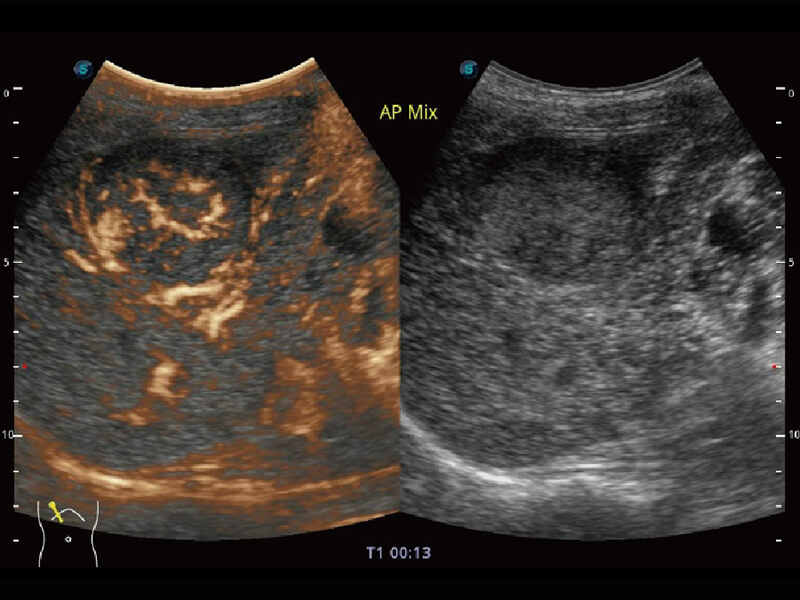

高分辨率容积成像 栩栩如生

超宽频带技术,为容积成像带来优质的二维图像基础,为您呈现丰富的结构细节,栩栩如生地展示宝宝的宫内形态以及各种组织的立体结构。